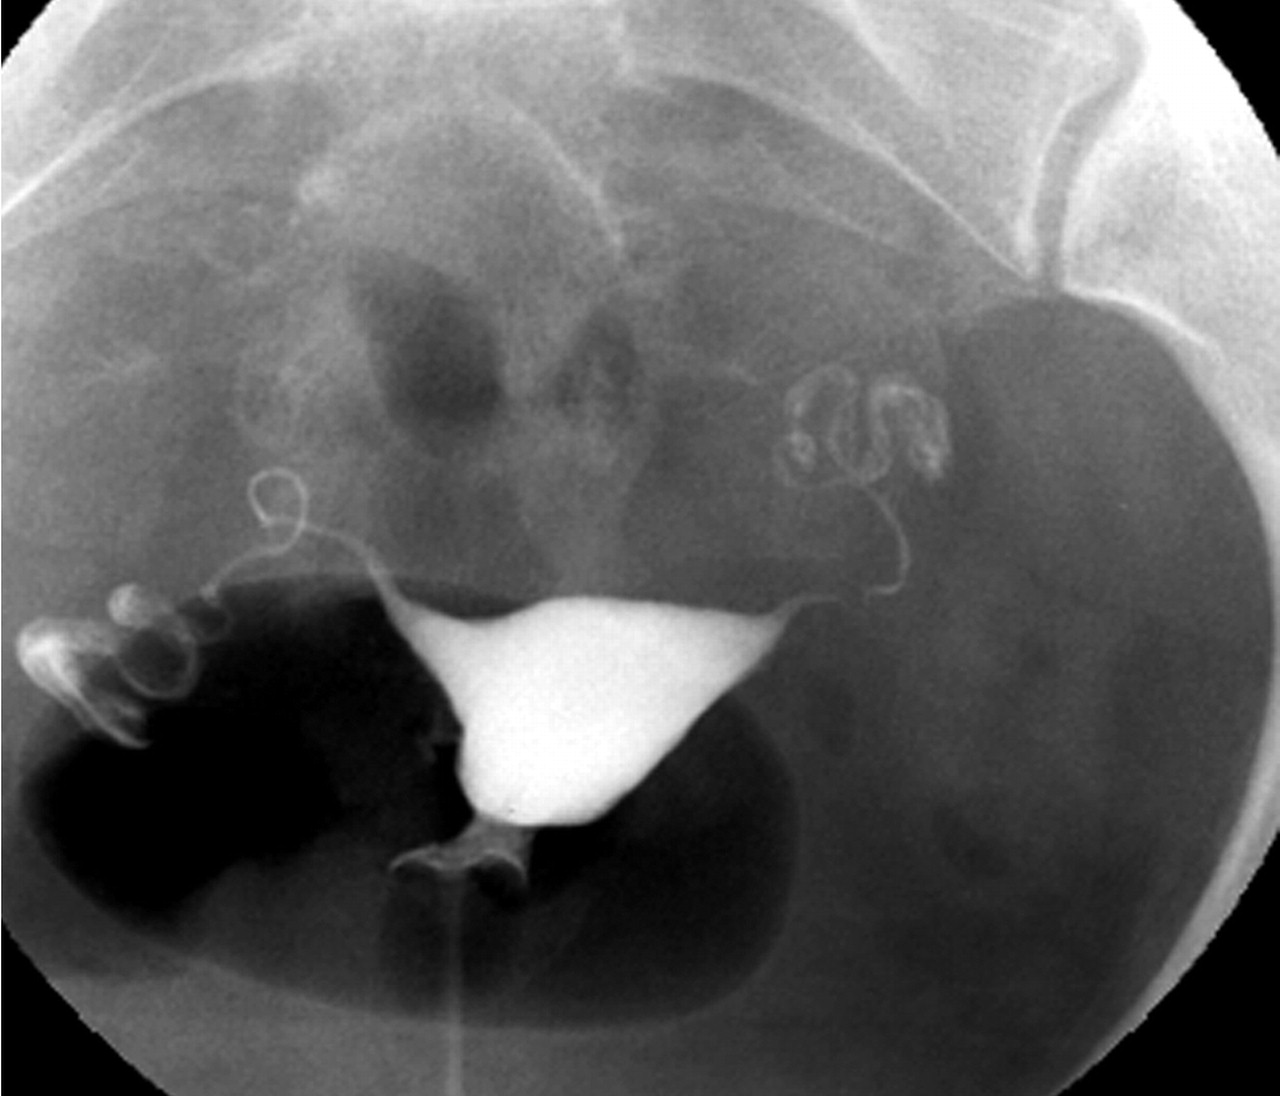

자궁경관에서 자궁강내에 조영제(造影劑)를 주입하고 자궁경관과 자궁강의 크기와 형상, 난관의 소통성, 골반복막의 상황, 유착의 유무, 난소종양의 유무 등을 X-선상(線像)으로 진단하는 방법이다.

⇒ 보통 자궁난관조영술은 자궁 및 난관(나팔관)에 조영제를 사용해서 자궁안쪽에 혹은 없는지 그리고 자궁의 크기나 모양은 괜찮은지 마지막으로 나팔관이 막혀있지는 않은지 등을 조영제를 사용해서 확인하는 방법이다.

사진을 보시면 자궁경부 입구  주사기 안에 들어 있는 조영제를 순차적으로 점점 밀어 넣게 됩니다.

그래서 만일 나팔관이 막혀 있지 않다면 자궁안을 채우고 난 이후 나팔관으로 순차적으로 조영제가 빠져 나가는 것이 확인이 되겠지만, 만일 자궁에 혹이 있는 경우엔 그 부분이 검게 뚫어져 있을 것이고, 나팔관이 막혀 있다면 나팔관 바깥쪽으로 조영제가 빠져 나가질 않을 것입니다.

그림1. 정상 나팔관 모습          그림2. 한쪽 나팔관이 막혀 있는 모습